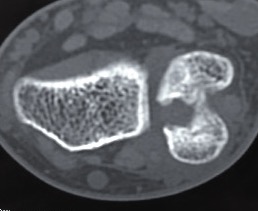

DRUJ instability

Post traumatic distal ulna osteoarthritis